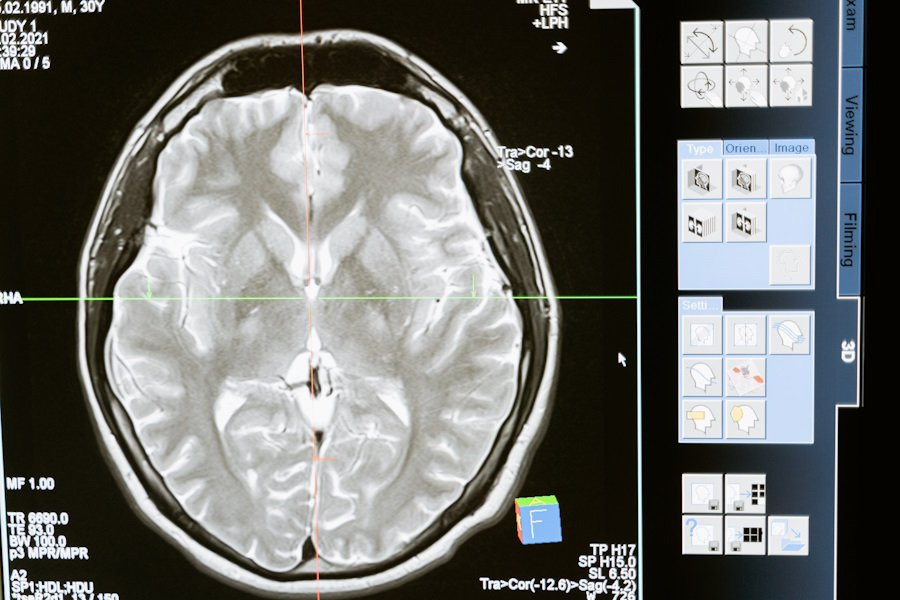

Нейробиологи из Northwestern University в США представили свои последние открытия, которые существенно изменяют наше понимание о том, как воспаление мозга воздействует на память. Согласно порталу Nature, исследование показывает, что воспаление нейронов головного мозга и повреждение ДНК могут играть положительную роль в формировании долговременных воспоминаний.

Ранее считалось, что воспаление нейронов может быть связано с риском развития болезней, таких как Альцгеймер и Паркинсон. Однако, новые исследования показывают, что воспалительные процессы в области гиппокампа, важного центра для обработки информации о прошлых событиях, необходимы для создания воспоминаний.

Используя мышей в качестве модели, ученые провели серию экспериментов, чтобы понять, как формируется память. Они обнаружили, что путь TLR9, обычно связанный с иммунным ответом на патогены, активировался в нейронах гиппокампа из-за повреждения ДНК, а не из-за инфекции. Это указывает на то, что активация пути TLR9 в ответ на повреждение ДНК имеет решающее значение для формирования памяти.